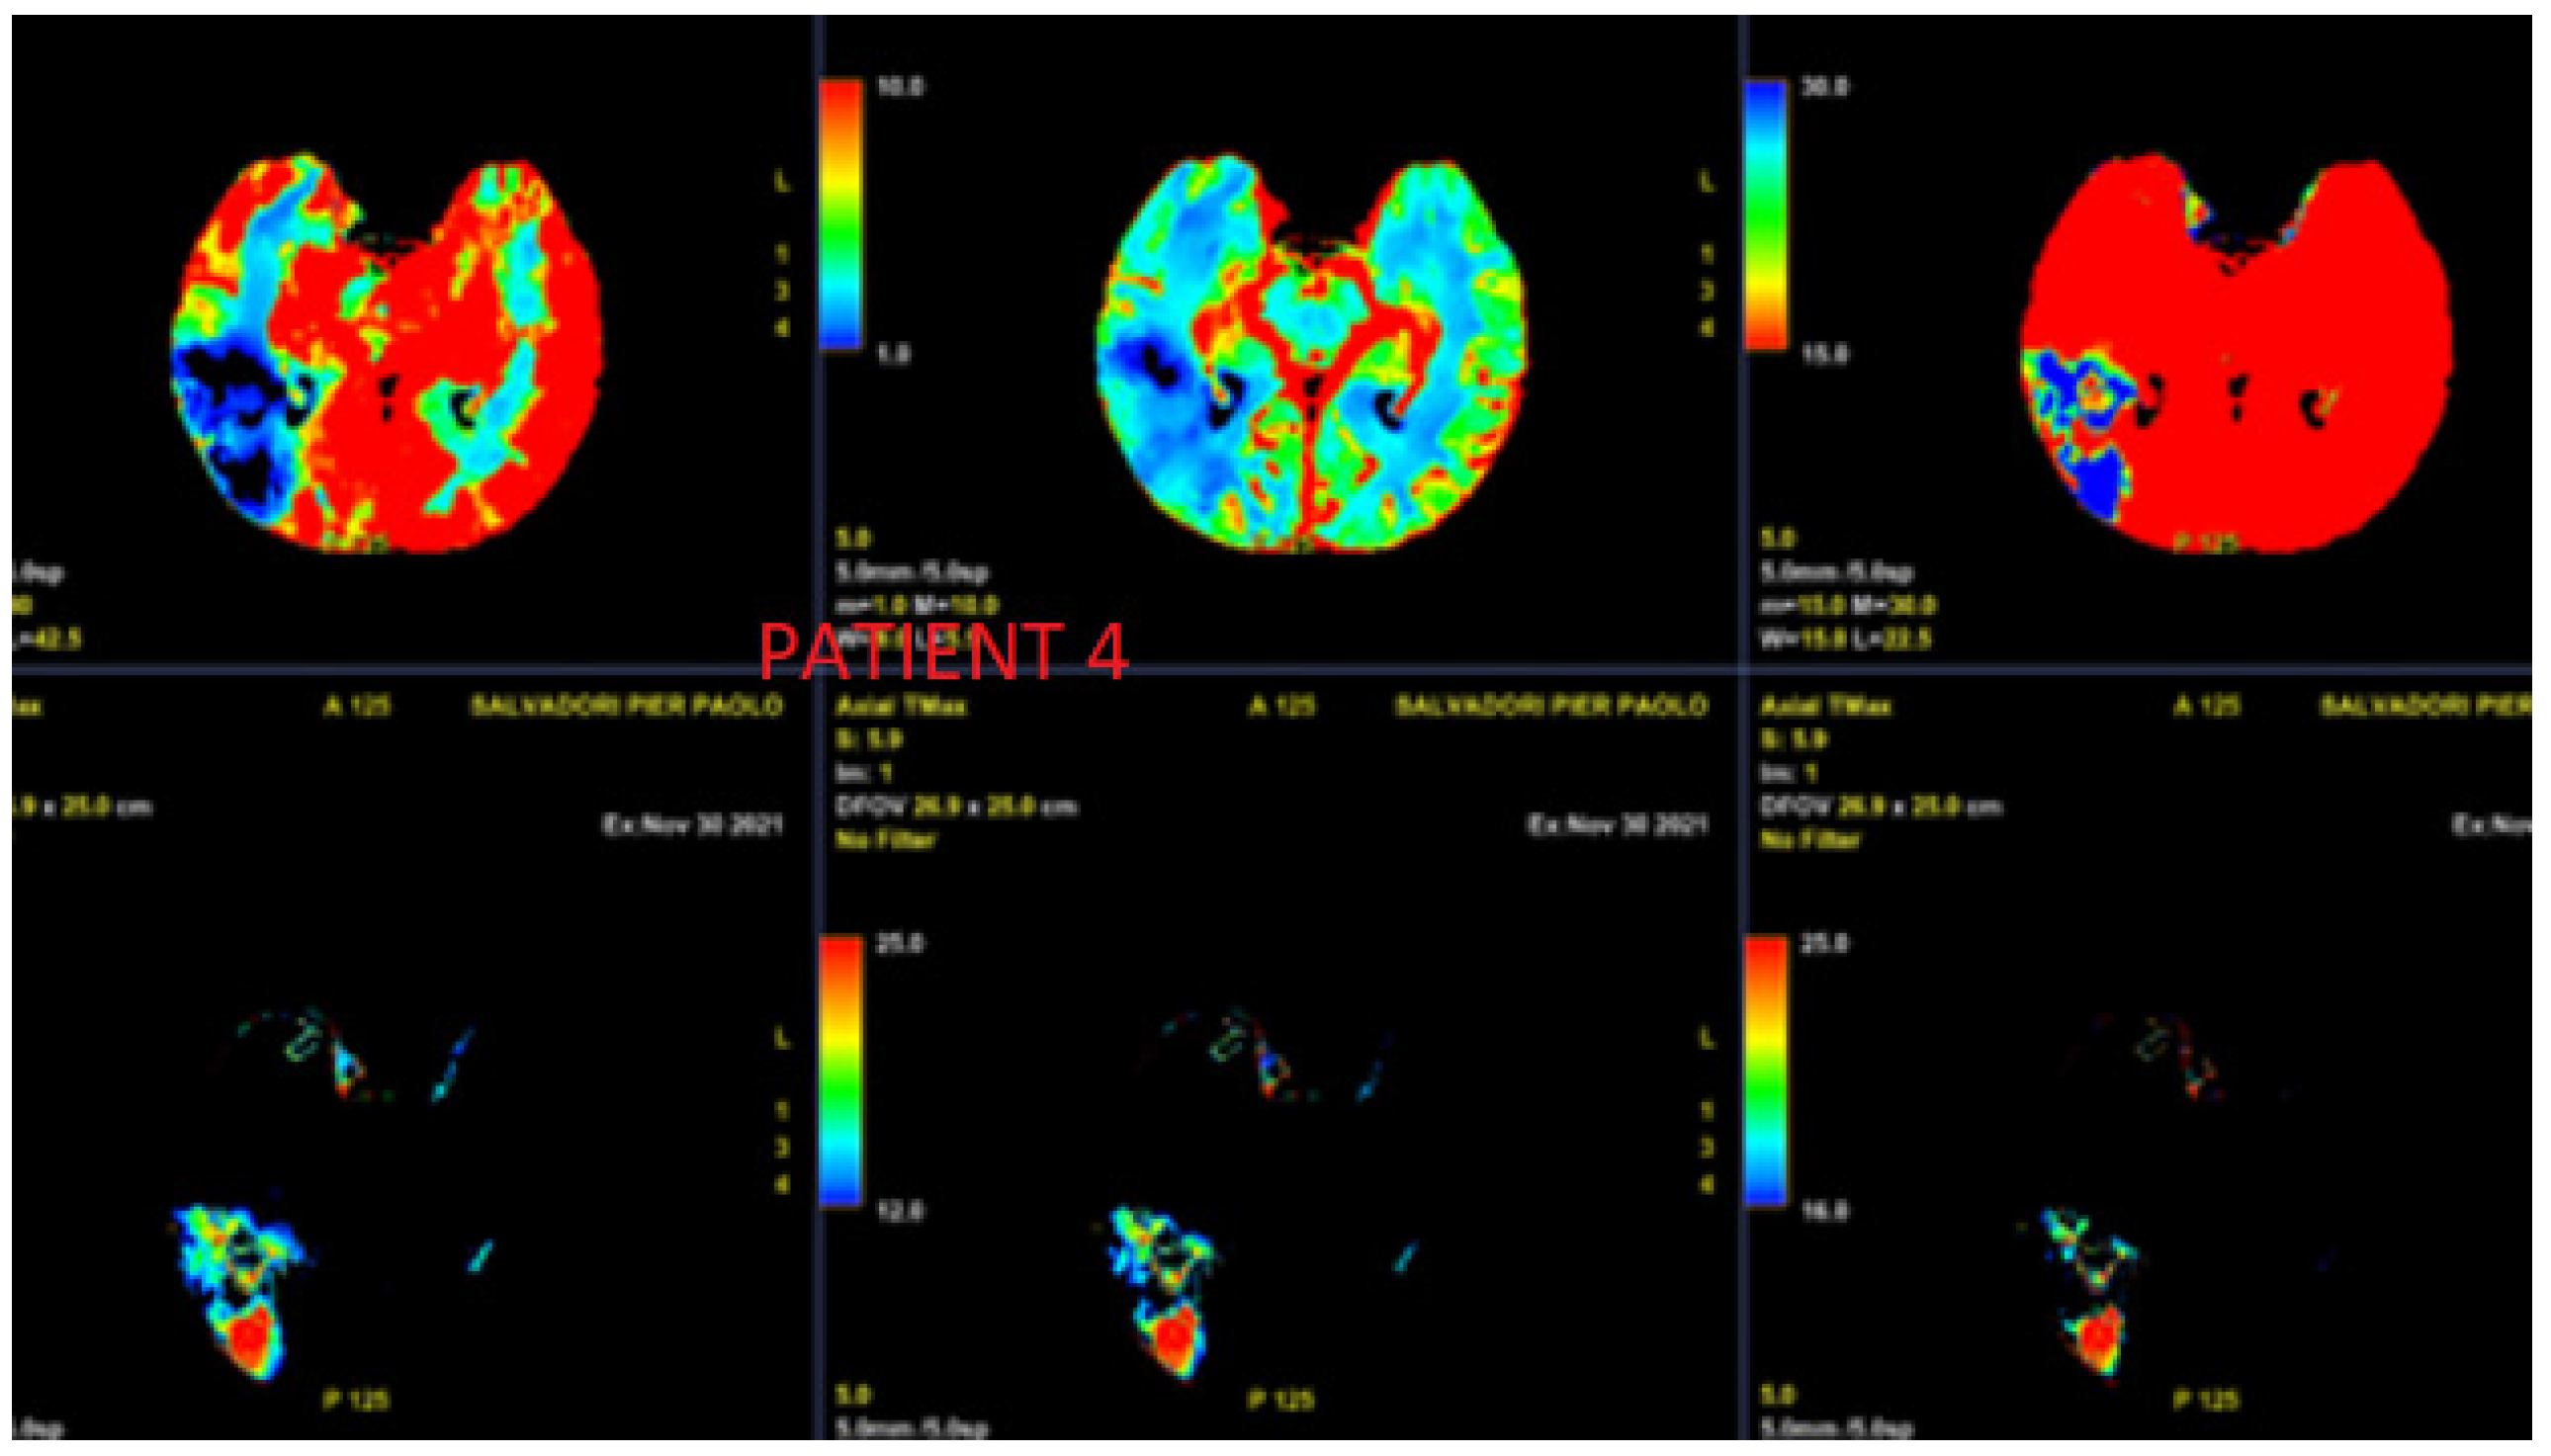

3.4. Case 4